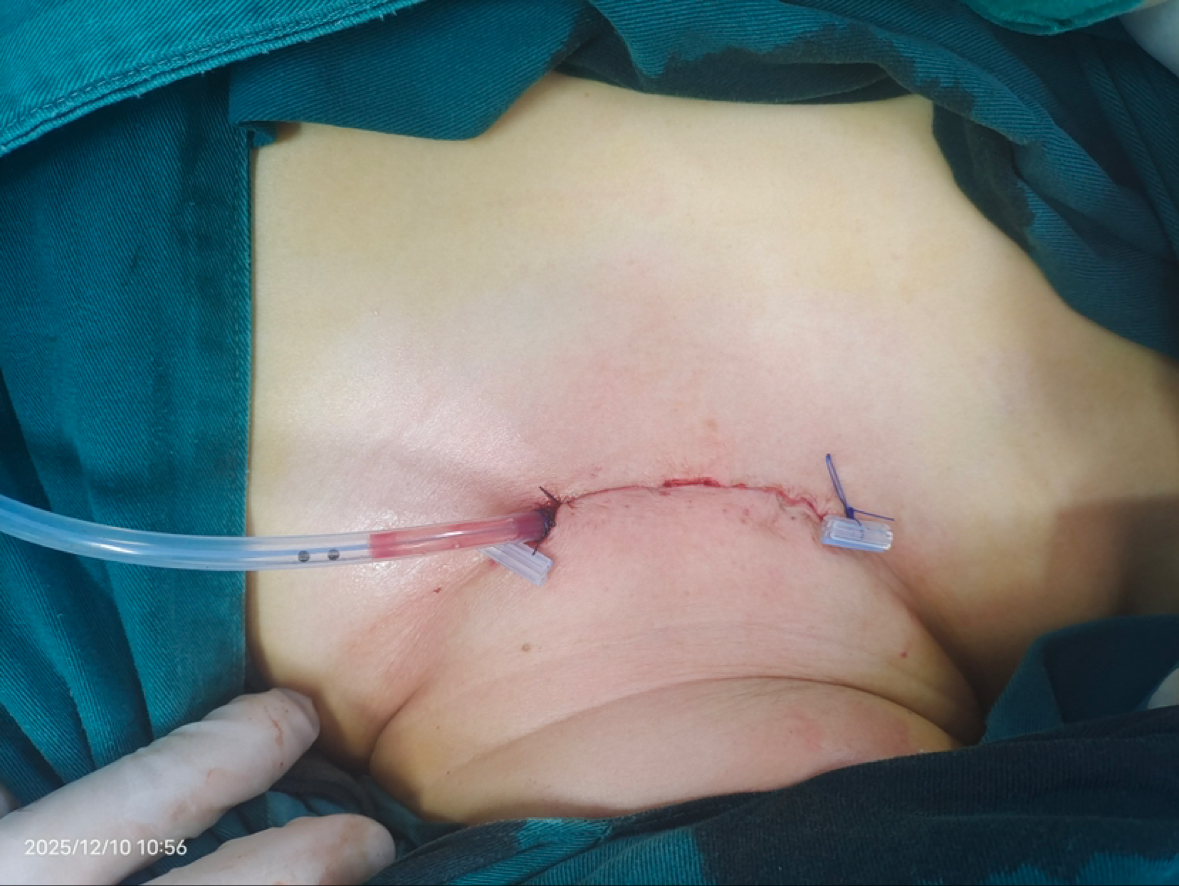

术后1天手术切口